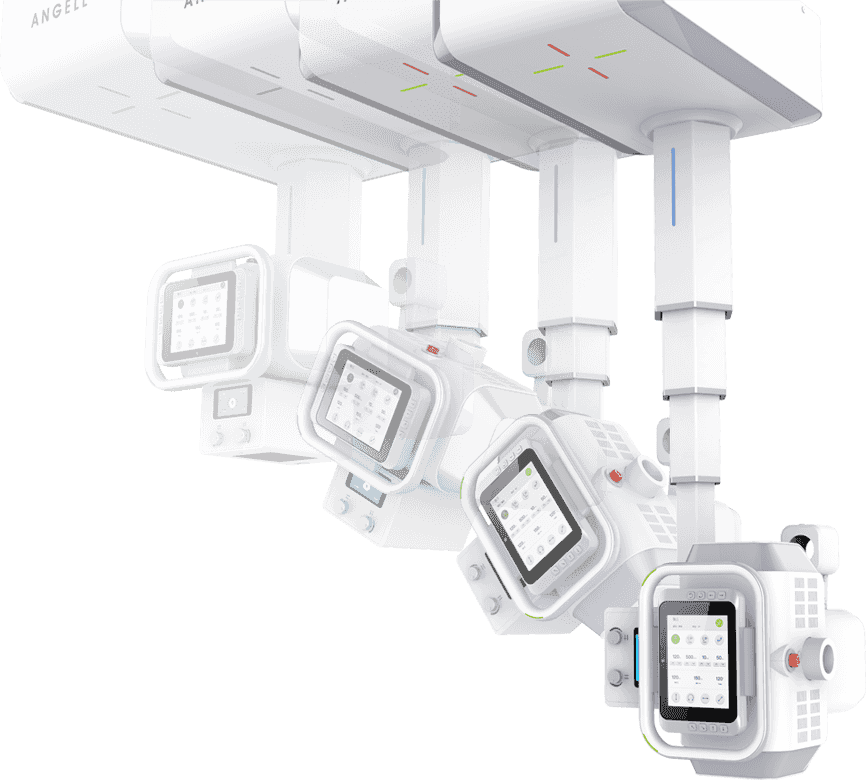

4D十轴联动运动系统

多功能悬吊式机械运动,全平衡稳定性设计,4D十轴联动技术,机架运动自如平稳,

配合电动升降床及多功能立式摄影架,轻松满足临床全体位摄影需求。

球管五向手自一体运动

采用手动与电动一体化设计,并具备感应驱动功能,

一键解锁即可轻松操控球管的全向运动。 -

智能触控大屏

液晶触摸屏,触摸操控设备运动,实时调整各类检查参数,

并同步显示患者信息、曝光参数及摆位提示。 -

任意键制动

一键切换运动过程中,任意键可停止设备运动,

保障运行状态安全可靠 -

任意键唤醒

自定义设置待机时长,任意键唤醒,环保节能; -